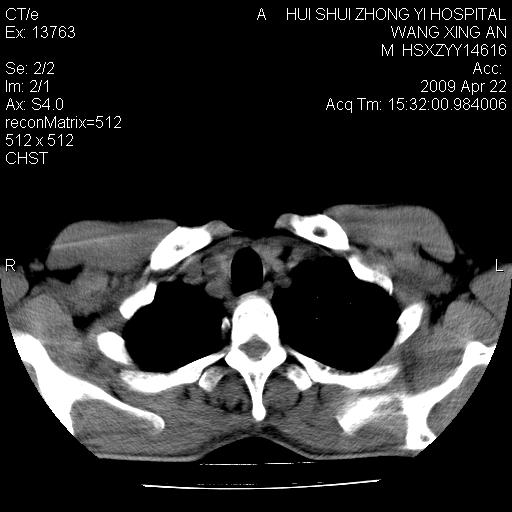

标题: CT19534:患者男、46岁咳嗽、胸痛半月。 [打印本页]

标题: CT19534:患者男、46岁咳嗽、胸痛半月。

右侧中心性肺癌并下叶肺不张,双肺及纵隔淋巴结转移,右侧胸腔积液

1、右下肺中央型肺癌并右肺转移,右肺中下叶不张。(右肺有结节影)。胸骨转移